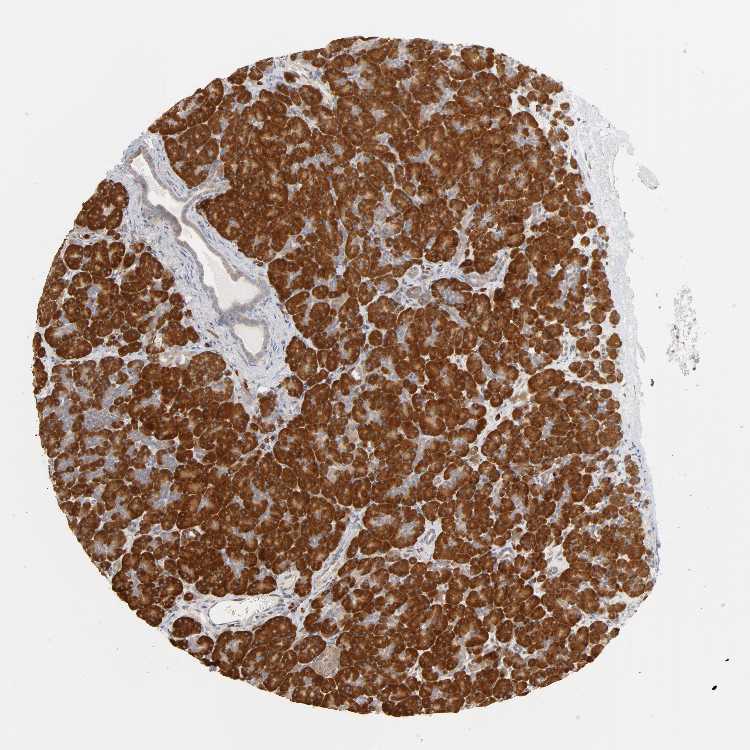

PANCREAS - Antibody stainingi

Antibody staining in the annotated cell types in the current human tissue is reported as not detected, low, medium, or high, based on conventional immunohistochemistry profiling in selected tissues. This score is based on the combination of the staining intensity and fraction of stained cells.

Each image is clickable and will lead to virtual microscopy that enables deeper exploration of all samples and also displays staining intensity scores, fraction scores and subcellular localization as well as patient and tissue information for each sample.

Antibody HPA003243Antibody HPA003445

Exocrine glandular cells HighHigh

Pancreatic endocrine cells LowMedium